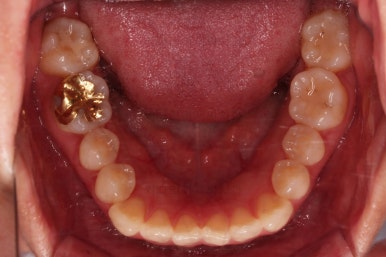

1. 초진

초진 시 입안의 모습입니다.

덧니가 눈에 띄고요.

맞물림이 긴밀하지 못한 상태였습니다.

전반적으로 약간 삐뚤지만 많이 심하다고 보긴 힘들었습니다.